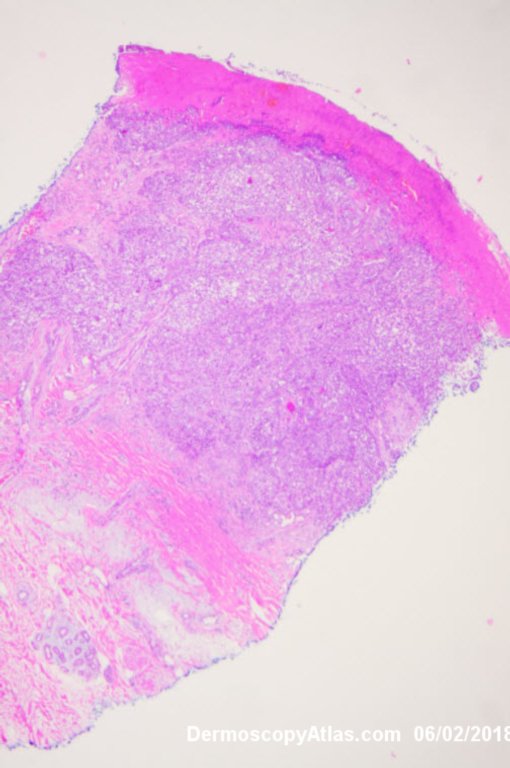

Image Number #3421 (Melanoma invasive)

Site: Leg

Diagnosis: Melanoma invasive

Description: Multiple colours in this pigmented lesion on the lower leg. New pink area

Lady in her early 80s who presented with this lesion on her ankle. The pigmented area had been there for some time but the pink area was bleeding and new. Shave of surrounding area and a punch biopsy of the new pink area showed mainly surrounding in situ melanoma with invasive melanoma in the pink area 1.8 mm thick. Having a 2cms margin excision of the whole area and a graft.